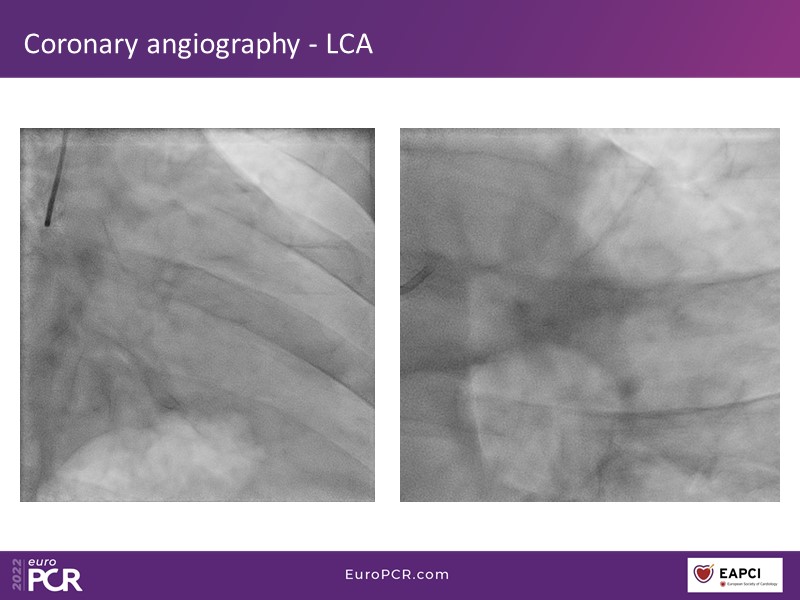

How to select three-vessel disease patients eligible for PCI and guide the treatment by angiography-derived physiology

- To select the lesions to be treated by angiography-derived physiology (quantitative flow ratio)